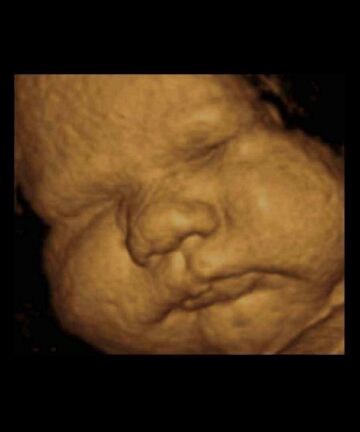

恭喜!你的胎儿从一个小细胞发育到2亿个细胞。40周出生的宝宝平均体重在3.3~4千克左右,身长大概有51厘米。

胎儿内脏和神经系统功能已经健全,手脚肌肉发达,富有活力,脑细胞的发育基本定型。胎儿的胸部会变得更凸出,由于肝在血红细胞生产中的特殊作用,胎儿的肝会自然变大。

别指望刚生出来的宝宝像洋娃娃那么可爱,新生儿头部通常都是暂时的畸形(通过产道时挤压所致),浑身覆盖着胎脂和血液,还可能肤色不匀,有胎记或皮疹,这些现象都是正常的。